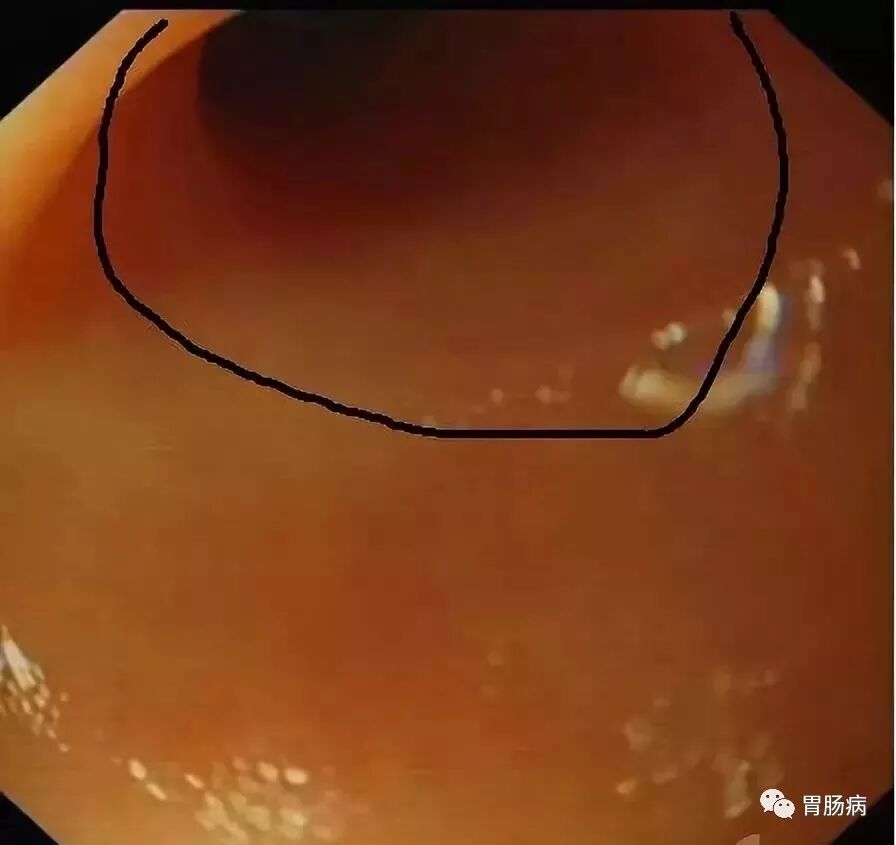

X线下,阑尾腔内注入造影剂显示阑尾腔的形态(椭圆形线圈),如有粪石(黑箭头),则行球囊取石术。并确认有无阑尾穿孔。